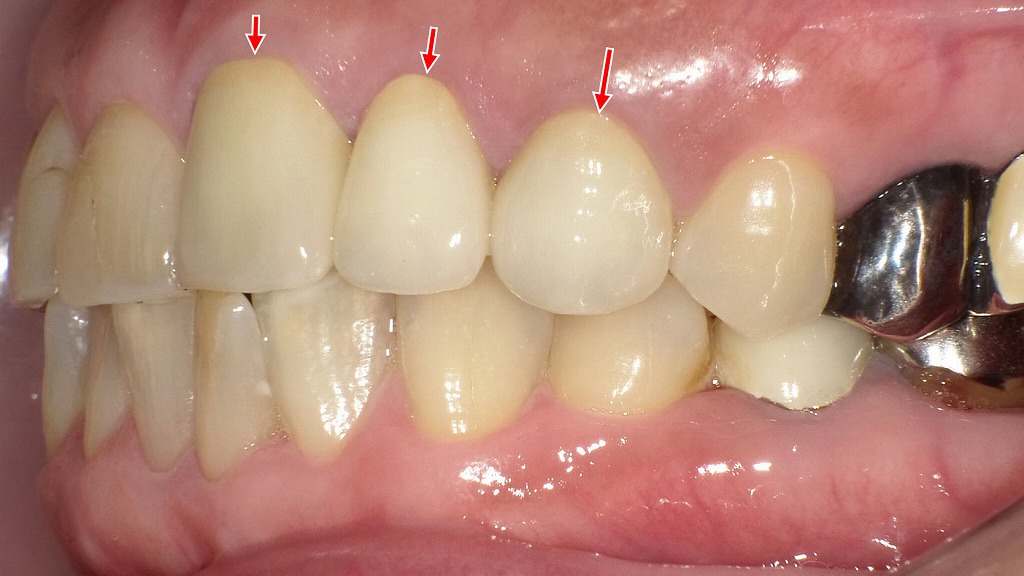

ジルコニアセラミッククラウンを装着した症例:側面観

この画像は、左上の第2小臼歯(通称「左上5番」)にジルコニアセラミッククラウンを装着した症例を示しています。以下に詳細を解説します。

🦷 対象歯(赤矢印部)

赤い矢印で示されている歯が左上5番(上顎第2小臼歯)です。

この歯にはジルコニアセラミック冠が装着されています。

💎 ジルコニアセラミックの特徴

- ジルコニア(内側):高強度で耐久性があり、金属アレルギーの心配がない。

- セラミック(外側):天然歯に近い透明感と色調を再現できる。

- 審美性と機能性を兼ね備え、奥歯でも長期間安定した使用が可能です。

👁️🗨️ 見た目の特徴

- 周囲の天然歯と色調・形態の調和がとれています。

- 歯頚部(歯ぐきとの境目)も自然で、歯肉の炎症や段差が見られません。

- 光の反射も自然で、人工歯特有の違和感が少ない仕上がりです。

⚙️ 機能面

- 咬合関係(上下の歯のかみ合わせ)も良好で、機能的な補綴物として適正に調整されています。

- 隣在歯との接触も自然で、**食片圧入(食べかすが挟まること)**が起きにくい設計です。

🩺 総評

この症例は、審美性・適合性・機能性のバランスがとれた良好な補綴治療例です。

ジルコニアセラミックは、特に金属を使いたくない方や自然な見た目を重視する方に適した選択肢です。